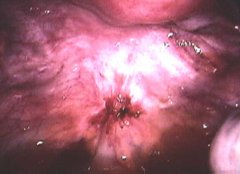

怀孕四个月胎儿彩超

胎儿没什么问题建议不要做B超。这个不好排除,做彩超也只能看胎儿肢体和器官发育而已对大脑跟本没办法了解所以你要好好养胎生下就知道了一般来说不会有什么问题的

我怀孕八个月了还没做过四维彩超现在八个月还有必要做吗?大概多少钱? 收藏 答案(4) 做应该好做的,不过我们当时检查的时候医生说有些畸形筛查过了24周四维就查

已经8个月了,医生建议可以去做个胎儿心脏检查,是四维彩超,不知道是不是只要是8--9个月之间都可以,会不会对胎儿有影响!

您好,现在都已经是8个月了,做四维彩超没有什么意义了。指导意见:都快到预产期了可以做个普通的彩超就可以确定是否对孩子产生影响的。因该是不会有什么问题的。

怀孕六个月做四维彩超发现胎儿左侧眼球内下 怀孕八个月做四维彩超显示胎儿双顶径只有6 我现在怀孕五个月做四维彩超结果说小孩8两 怀孕六个月做四维彩超一切正常就

怀孕八个月做四维彩超显示胎儿双顶径只有6.9cm,股骨长5,7cm,双顶径太小了怎么办? 怀孕八个月做四维彩超显示胎儿双顶径只有6.9cm,股骨长5,7cm,双顶径太

我怀孕到现在快8个月了没做过四维彩超,就做过产前筛查,还需要去做四维彩超吗?大概需要多少费用?我怀孕到现在快8个月了没做过四维彩超,就做过产前筛查,还

我现在怀孕五个月做四维彩超结果说小孩8两,大夫说小孩小,到底多重正常 怀孕六个月做四维彩超胎儿后颅窝池深0。7 怀孕五个月做四维彩超能看到孩子的